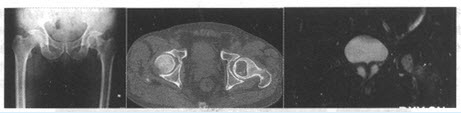

患者,女,30岁。左髋不适2个月余。X线、CT及MRI检查如下。

(单选题)首先诊断()

A:骨母细胞瘤

B:骨巨细胞瘤

C:内生软骨瘤

D:软骨黏液纤维瘤

E:软骨母细胞瘤